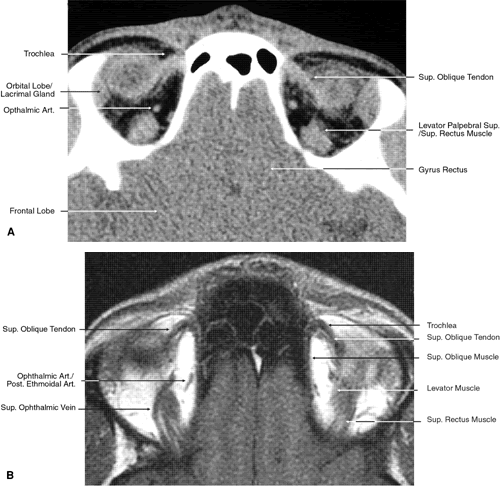

The globe is shown in Figure 12. The orbit and periorbital structures are shown in Figures 13 through 16, and the optic canal is shown in Figures 17 through 26. The cavernous sinus and optic chiasm are shown in Figures 27 and 28, and the posterior visual pathway and cranial nerves are shown in Figures 29 through 33.

Fig. 24. Axial images at the level of superior orbit. A. Computed tomography scan. B. T1-weighted magnetic resonance imaging.

Fig. 25. Axial images at the level of tendon of the superior oblique. A. Computed tomography scan. B. T1-weighted magnetic resonance imaging.